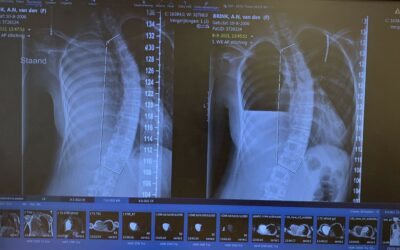

Vandaag moesten we naar het WKZ om foto's te maken van de rug en een gesprek met orthopeed Vergroesen. Het was vooral een oriënterend gesprek om te kijken of de scoliose erger is geworden en wat de plannen voor de toekomst zijn. Op de foto is duidelijk te zien dat...